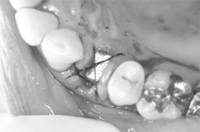

![]() |

抜歯と同時にオープンバリアメンブレン・テクニックをおこないました。お痛み・腫れはほとんどありません。